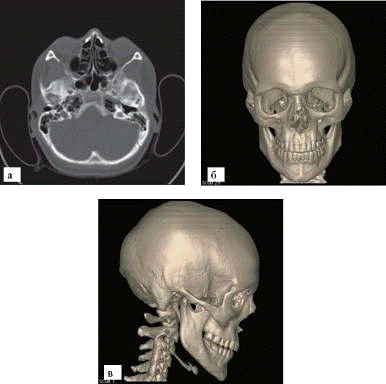

Обзорные рентгенограммы черепа в прямой и боковой проекциях являются основой для изучения костей мозгового и лицевого черепа (рис. 3)

Исследование затрудняет дифференцирование тканей, но все же удается различать множество анатомических структур. Толщина костей свода невелика - от 0,5 до 1 см. В области теменных и затылочных бугров кости толще, в области височной впадины - тоньше.

Рис. 5. МСКТ черепа: а - поперечный срез; б - трехмерная реконструкция, вид спереди; в - трехмерная реконструкция, вид сбоку ференцируются борозды оболочных артерий, каналы и звездчатые разветвления диплоэтических вен и пахионовых грануляций, а также пальцевые вдавления. Отдельные кости черепа соединяются между собой разного вида швами. В черепе ребенка места с неоконченным окостенением называются родничками.